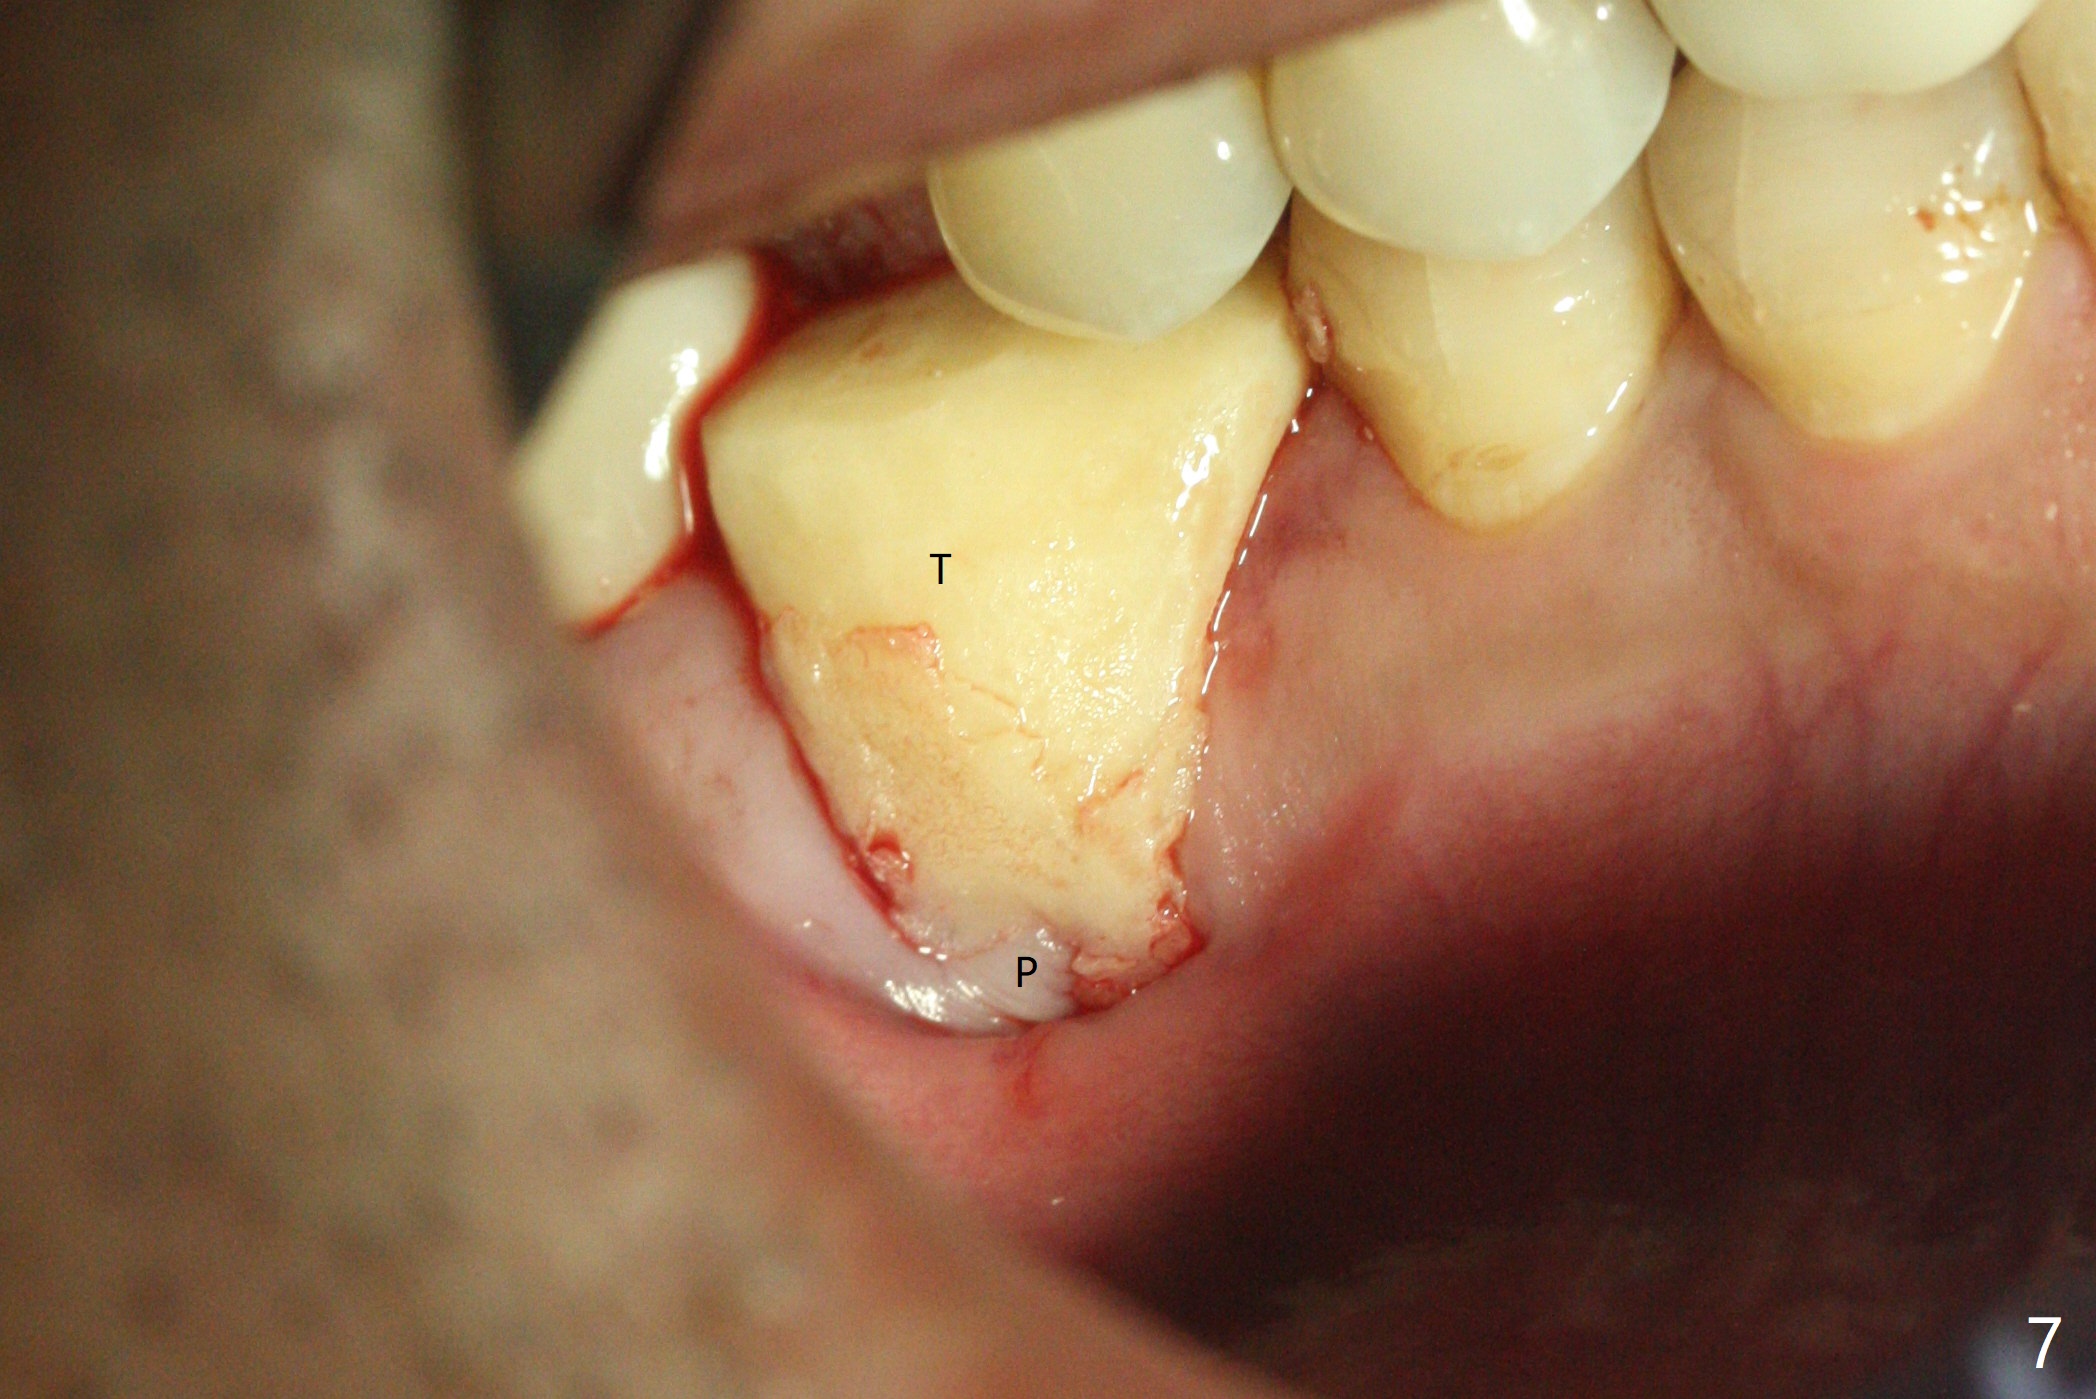

When the tooth #30 is extracted, the gingiva buccal to the septum (S in Fig.1,2 (P: papilla between the mesial and distal roots)) collapses. The latter is fixed with placement of a 4.5x11.5 mm implant (with guide), a 5.2x4(5) mm cemented abutment (Fig.3) and mixture of cortical bone (125μm – 850μm) and cortical/cancellous bone (.5-1 mm) with PRF (sticky bone, B in Fig.4-6). After placement of 2 pieces of PRF membrane over the bone graft, a temporary crown is fabricated to cover the buccal defect (Fig.7 T). Approximately 7.5 mm of the buccal threads are covered by the thick layer of bone graft (Fig.8 B). It is amazing to expect that the bone graft will turn into the buccal plate. It would be better if a narrower implant (4 instead of 4.5 mm) were placed more lingually or there were < 4 mm implant thread exposure (Fig.9). The gingiva reacts to the provisional nicely 7 days postop (Fig.10). The provisional will be removed for modification in 1 month. The patient complains of bad smell from the provisional 2 weeks postop. The provisional is removed. The distal socket (Fig.11 D) is healing, whereas the buccal bone graft (Fig.12 B) seems not have been vascularized. Pedicled flaps (I) should be transferred to cover the buccal bone graft. The margin of the provisional is polished, becomes short, and covered by periodontal dressing, which dislodges 2 days later. One week later, granulation tissue is forming apically with use of oral antibiotic and water jet (Fig.13 *). The bad smell reduces. The superficial loose bone graft changes colar and becomes detached 1 month 10 days postop. The temporary crown with the shortened buccal shelf is reseated for self cleansing or reapplication of PRF if needed (Fig.14).